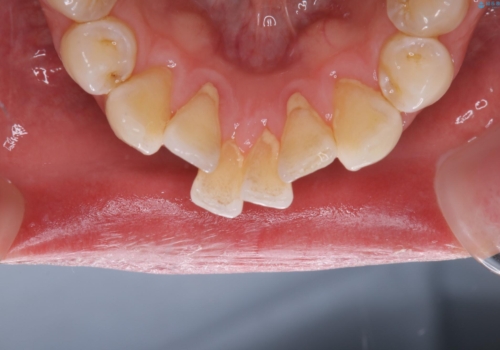

PMTCを初めてやったとのことで、全体的にステイン、プラーク、歯石が多く付着していました。これから虫歯の治療や矯正がスタートするため、歯茎が腫れていたり、汚れが付着していると、虫歯や歯周病が進行してしまうため、治療と並行してブラッシング指導、クリーニングを行っています。何よりも日々のクリーニング(ホームケア)が大切なため、頑張っています。

定期的なクリーニングを行っていても、毎日しっかりと磨けていなければ虫歯も進行しますし、まずはブラッシングの仕方、デンタルフロスと徐々にステップアップしていきます。